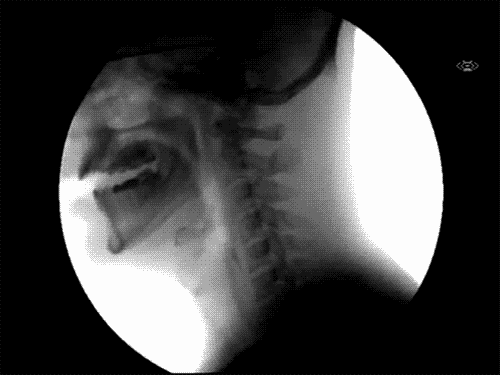

Deglución

- En la deglución intervienen múltiples sistemas funcionales y estructuras corporales: estado de conciencia, cavidad oral, estructuras óseas, tejidos blandos, pares craneanos (V, VII, IX, X, XI y XII), postura y sostén de tronco. Algunas pruebas permiten evaluar la deglución sin equipos especiales: test de deglución en seco, test de deglución repetitiva de saliva, test de deglución de agua, test de agua coloreada, auscultación cervical de la deglución y el test de provocación de la deglución.

- Se considera que si un paciente puede beber 50 ml de agua sin dificultad, posiblemente no tendrá un problema serio de disfagia.